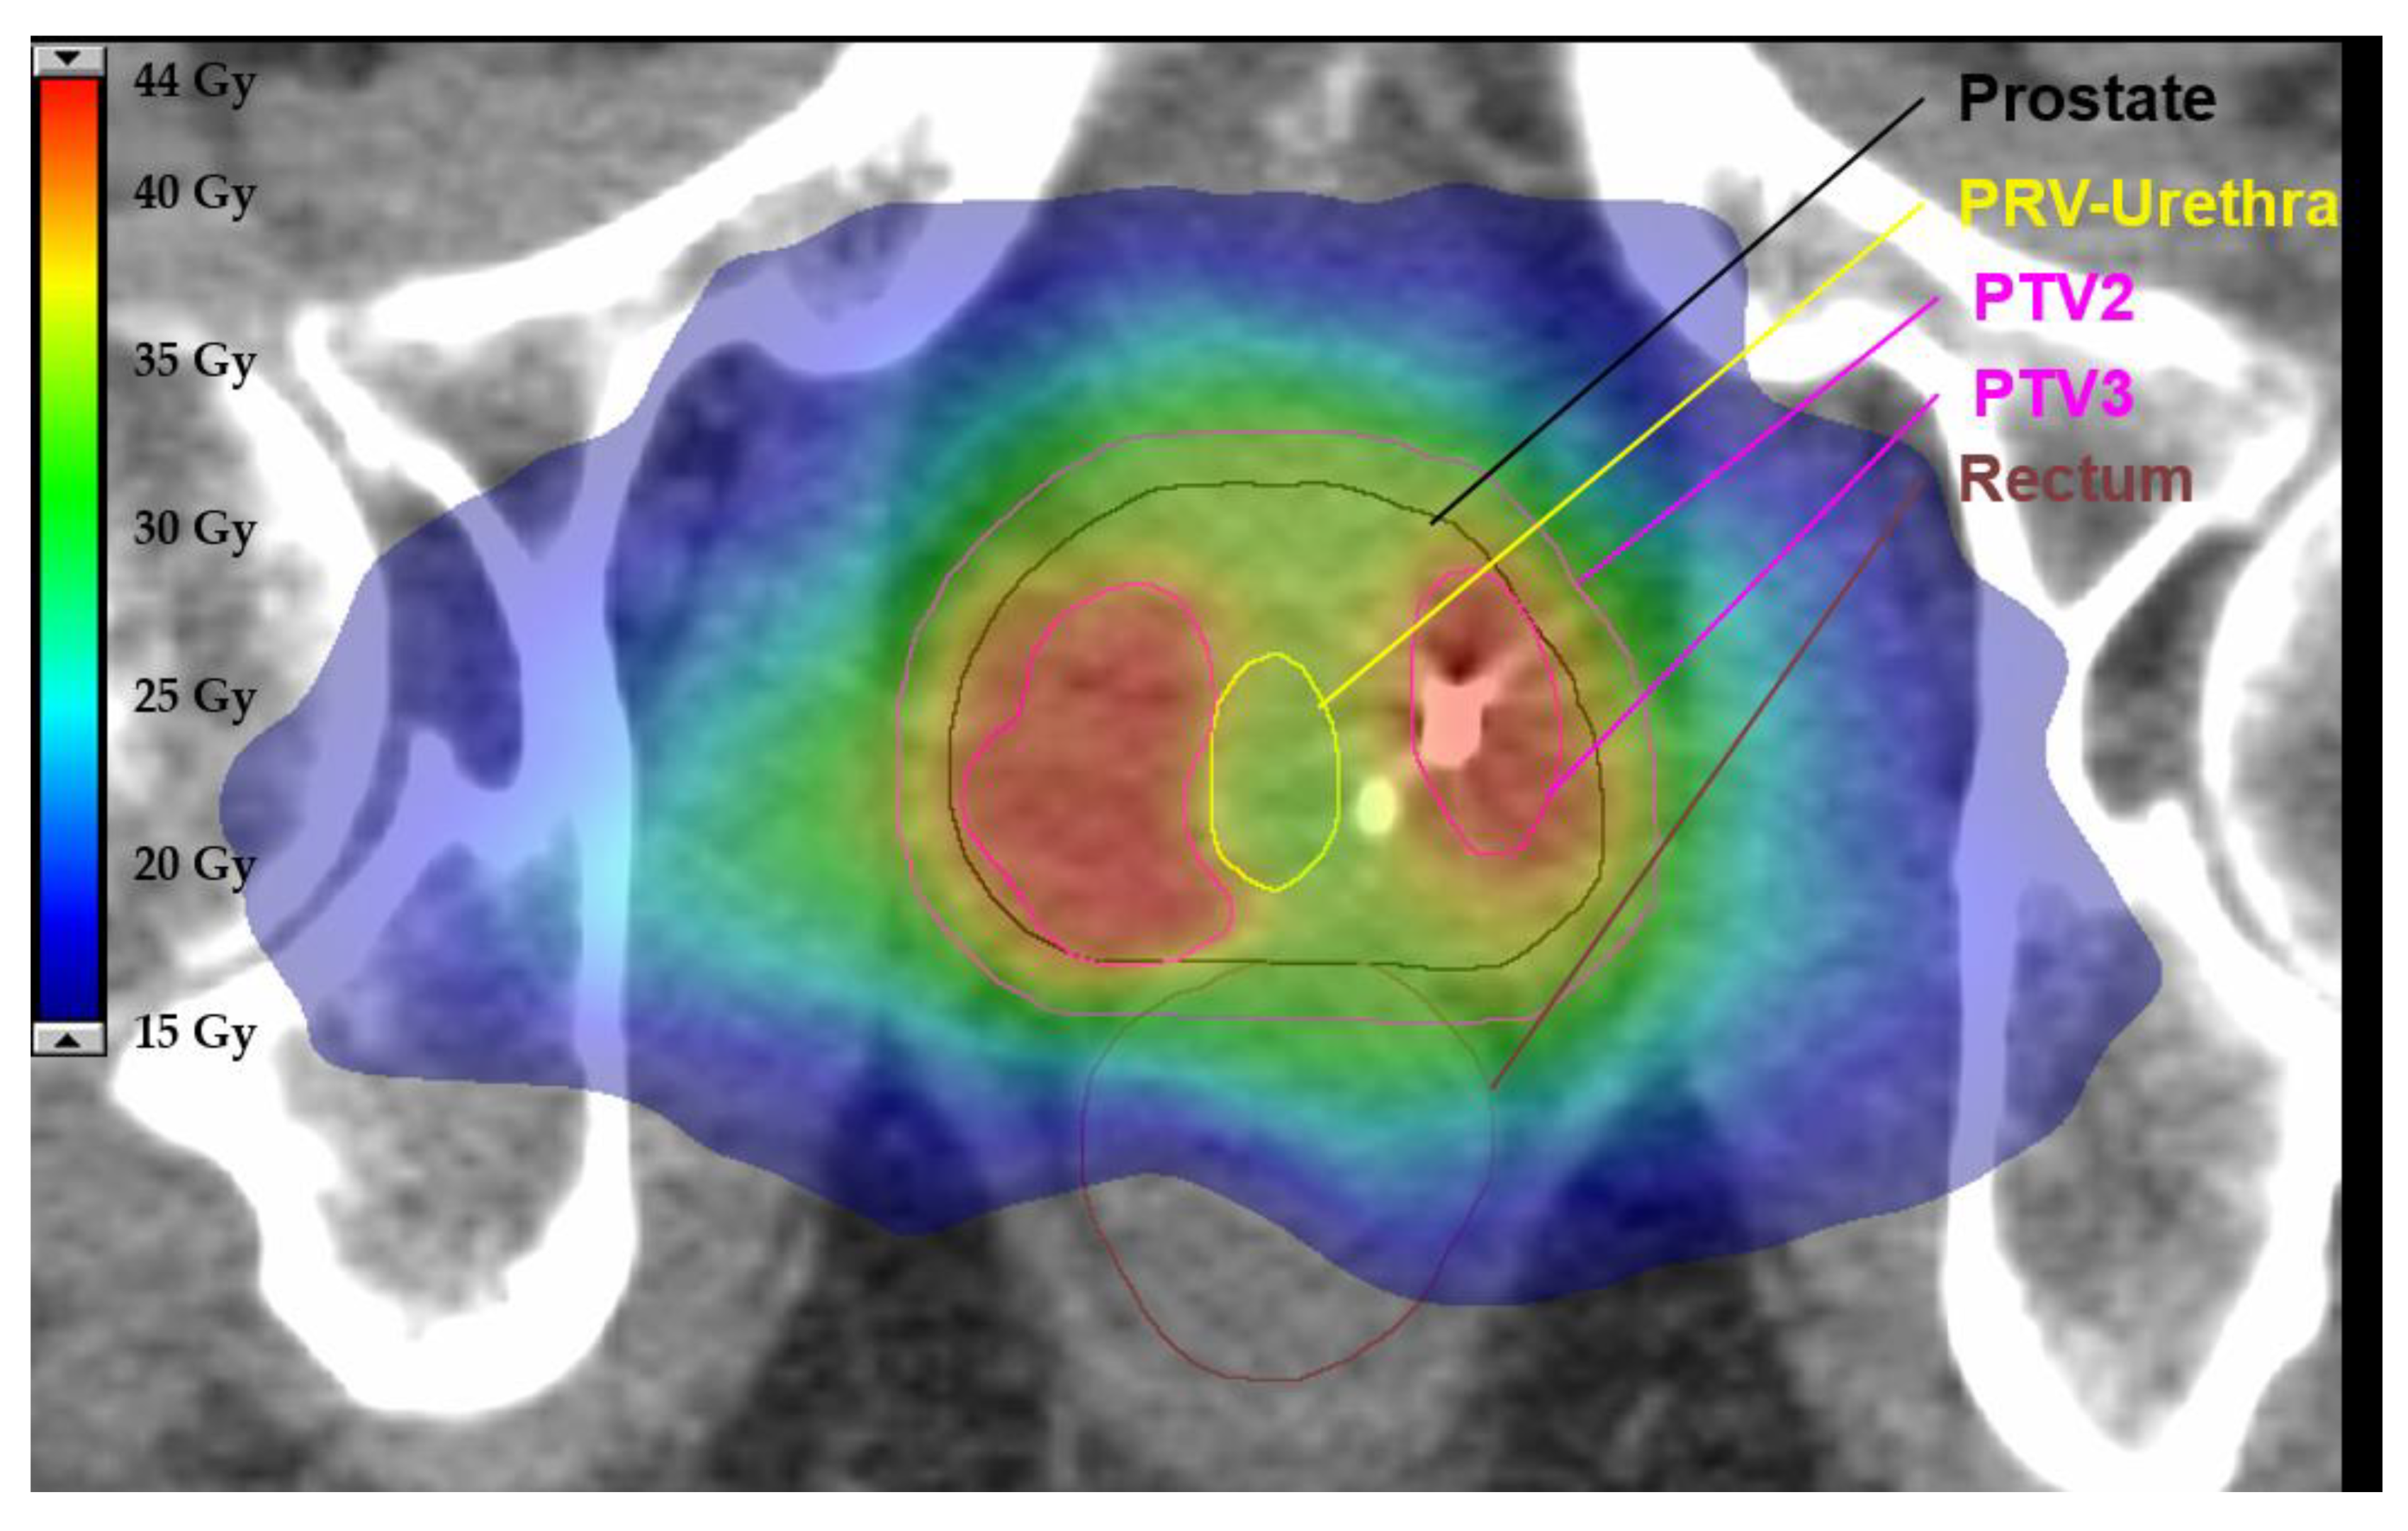

For the experimental arm (SBRT) PTV1 is created by the addition of CTV1 and CTV_SV and 4 mm isotropic expansion (see Figure 1a,b). PTV 2 is created by 4 mm isotropic expansion of CTV 1 (see Figure 1c). PTV3 is created by 0–2 mm isotropic expansion of GTV-union. PTV3 must not overlap with the PRV-Rectum, PRV-Rectum_adapt, Bladder or PRV-Urethra contours. In this case, the overlapping volume must be removed from PTV3 even if parts of the GTV are excluded (Figure 2a–c).

Figure 2.

Definition of PTV3 for SBRT. Planning target volume 3 (PTV3) is created by of 0–2mm isotropic extension of the gross tumour volume (GTV) (a,b). Overlapping parts with planning organ at risk volume (PRV) of rectum and urethra are removed from PTV3 (c).

For the definition of PTV3, the GTV-union (Figure 3, a, green), merged by using all delineated GTVs, is extended by an isotropic margin of 0–2 mm (b). Organs at risk (OARs) are delineated (a): bladder (yellow), urethra (dark yellow), rectum (orange/brown) and respective PRVs are created by isotropic expansion of 2 mm (b). The PTV-volume, overlapping with the PRV of either rectum or urethra, must be deleted from PTV3 even if parts of the GTV are excluded (c).

Figure 3.

Exemplary axial slide of a representative plan using stereotactic body radiotherapy (SBRT) for the experimental arm. This example demonstrates how overlapping parts between the planning target volume (PTV) and planning organ at risk volume (PRV) are removed to define the final PTV. There is a steep dose gradient to spare the urethra while preserving a sufficient dose to the PTV. Relevant organ as risks, PTVs and isodoses in colorwash are illustrated according to the legend.

Prescription doses for the PTVs and constraints for OARs in the experimental arm (SBRT) are provided in Table 2 and Table 3 [7,32,52,53,54]. Prescription doses for the entire prostate must be calculated in subtraction volumes of the PTV and the Boost-PTV (PTV3). Prescription doses are the following: For PTV1 (subtraction: PTV1–PTV3): 30 Gy in 6 Gy per fraction, and for PTV2 (subtraction: PTV2–PTV3) 35 Gy in 7 Gy per fraction. The prescription dose for PTV3 ranges between 40 and 42 Gy (see Figure 3). Initial planning should be performed with a prescription dose of 42 Gy and should be reduced up to 40 Gy in 1 Gy intervals when dose constraints are not met. In cases of large boost volumes (≥10 mL and/or ≥1/3 of the prostate), the dose to PTV3 must be restrained to 40 Gy in 8 Gy per fraction.